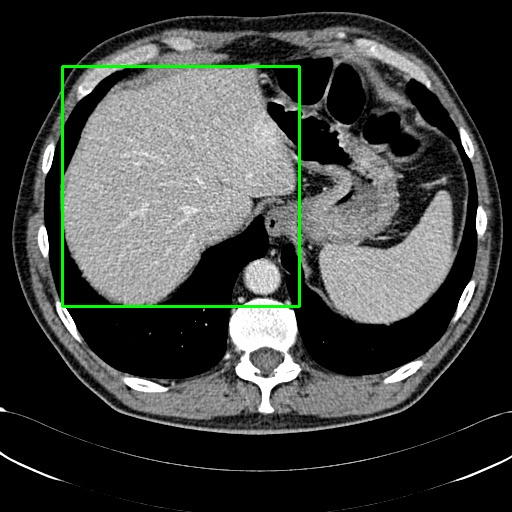

We employ appropriate strategies to locate ROIs for images paired with different annotations. For datasets that already include localization annotations, such as segmentation masks or bounding boxes, we derive the ROIs from these paired annotations. Specifically, bounding boxes are directly used as the ROIs, while segmentation masks are converted to ROIs by creating the smallest bounding box that covers the mask. When such localization annotations are not available, we apply corresponding pretrained expert models to generate ROIs. More details about the selection of expert models are provided in Appendix D. Examples of generated ROIs from various modalities using corresponding models are demonstrated in Figure 6. For modalities such as X-ray and MRI scans viewed from the z-axis, our ROI localization employs a coordinate system relative to the human body, resulting in a left-right reversal in the image representation.

Refer to caption

(a) Example of locating ROI via SAT (Zhao et al., 2023).

(b) Example of locating ROI via BA-Transformer (Wang et al., 2021).

(c) Example of locating ROI via Chexmask (Gaggion et al., 2022).

Figure 6: Example of ROIs and their corresponding textual descriptions.